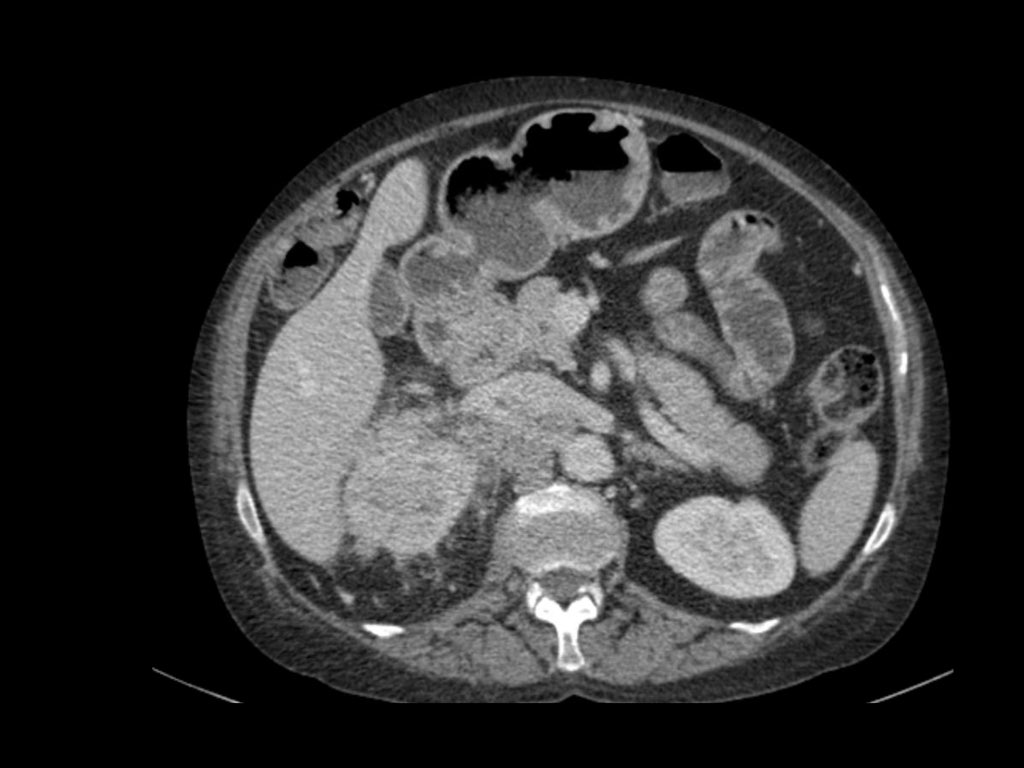

Phân giai đoạn RCC

RCC có thể xâm lấn mỡ quanh thận vượt qua cân thận và có thể lan vào tĩnh mạch thận, tĩnh mạch chủ dưới (IVC) hoặc tuyến thượng thận cùng bên.

Đối với phẫu thuật viên, điều quan trọng là cần biết có huyết khối u trong IVC hay không và liệu huyết khối có lan vào lồng ngực trên cơ hoành hay không (cần có phẫu thuật viên lồng ngực trong ca mổ).

Khoảng 25% bệnh nhân đã có di căn tại thời điểm chẩn đoán.